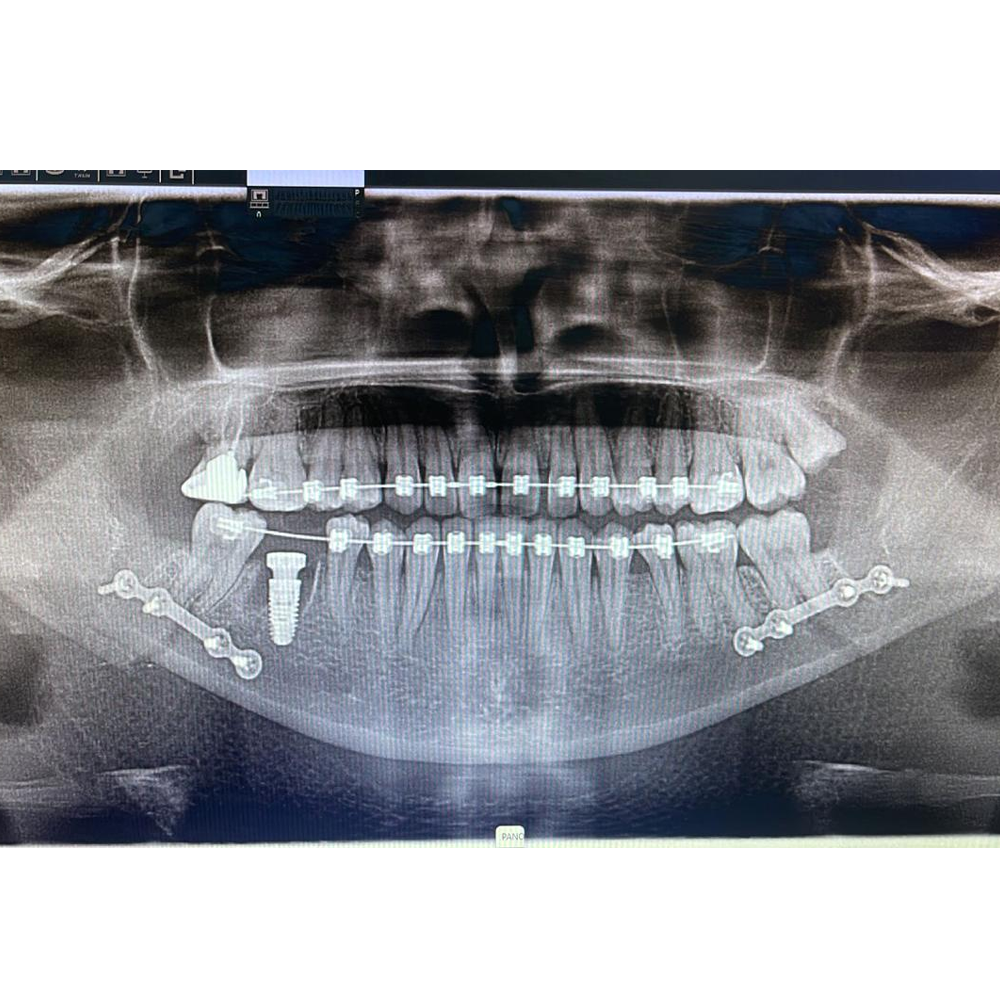

Orthognathic Surgeries

A forward or backward placed upper or lower jaw can have an immense impact on an individual’s oral health, personality and social life. These are known as skeletal malocclusion. In an age where certain jobs require a certain facial profile, such malocclusions can be a deterrent.

Orthognathic surgery answers these problems along with orthodontic therapy.

Utilizing these surgical techniques we can move a forwardly placed jaw backward and vice-versa.

At our center, we strive to diagnose such malocclusion and do orthognathic surgeries if required.